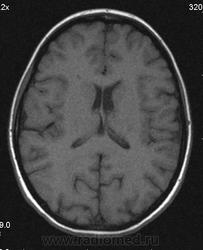

Можно ли  трактовать участок повышенного МР-сигнала по Т2 в правой лобной доле как участок перивентрикулярного глиоза?

Часто встречаемая структура, не задумывался что "это" конкретно, наверное Робин-Вирховские. В данном случае - изменения по-моему просто несколько асимметричны.

Большое спасибо. Да, симметричная линейная паравентрикулярная структура в области передних рогов встречается часто, на что обычно не обращаю внимания. В этом случае смутила ее асимметричность (особенно на Coг. срезах), если думать что это Вирхова-Робина, то возможно это слабо выраженный периваскулярный глиоз.

Иногда у пациентов с дисциркулятонной энцефалопатией по периферии расширенных периваскулярных пространств встречала линейное повышение нтенсивности МР-сигнала на Tirm, расценивала как периваскулярый глиоз, и у нескольких пациентов перенесших перинатальную энцефалопатию видела относительно симметричные зоны паравентрикулярного глиоза резидуального характера в области задних и иногда передних рогов. Поэтому и задумалась, увидив такую асимметричность интенсивности сигнала в этом случае, заподозрив "нерезко выраженный" глиоз справа.

1) господа МРТшники, если это расширенное вирхов-робиновское пространство, как вы объясните тот факт, что в TIRM последовательности сигнал от данного участка высокий?

2) данная находка (единичный мелкий дисциркуляторный очаг) имеет мало практической ценности. не описали бы - ничего страшного. такие перивентрикулярные изменения бывают у очень многих людей и тяготеют к норме для тех, кто старше 40 лет.

3) термин "глиоз" - гистологический, и применять его в лучевой диагностике некорректно, ИМХО.  в дисциркуляторных очагах помимо глиоза находят и другие изменения.